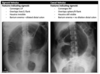

Sigmoid volvulus ## Footnote dilation causes the classic coffee-bean sign, a pathognomonic of sigmoid volvulus.